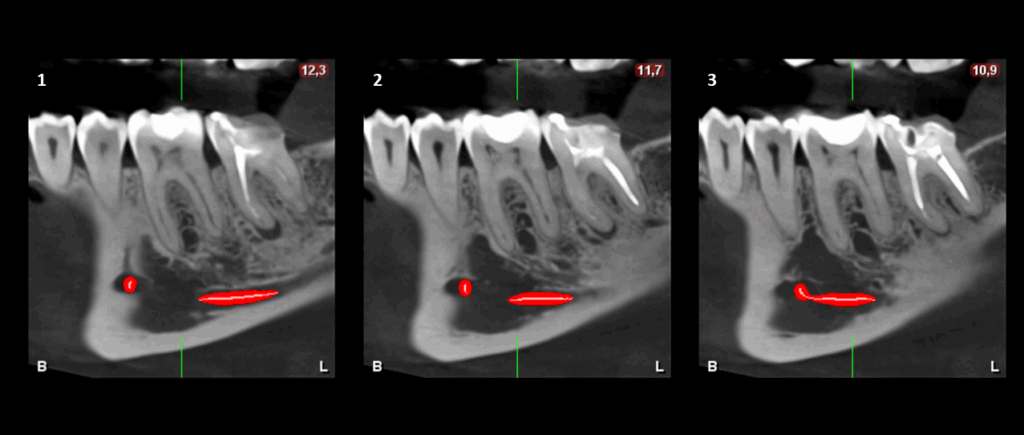

En el estudio complementario mediante tomografía computarizada de haz cónico (TCHC), se observa la obturación subextendida de conductos en la raíz mesial de la pieza 37, se confirma el proceso osteolítico periapical y el aumento de la densidad ósea circundante con extensión hacia el conducto dentario inferior. En la pieza 46 se observa una restauración oclusal hiperdensa con material restaurador isodenso subyacente próximo a cámara pulpar y se corrobora el aumento de la densidad ósea periapical que además se extiende hacia la tabla ósea lingual.

CORTES TRANSAXIALES

- Osteítis condensante en piezas 37 y 46.